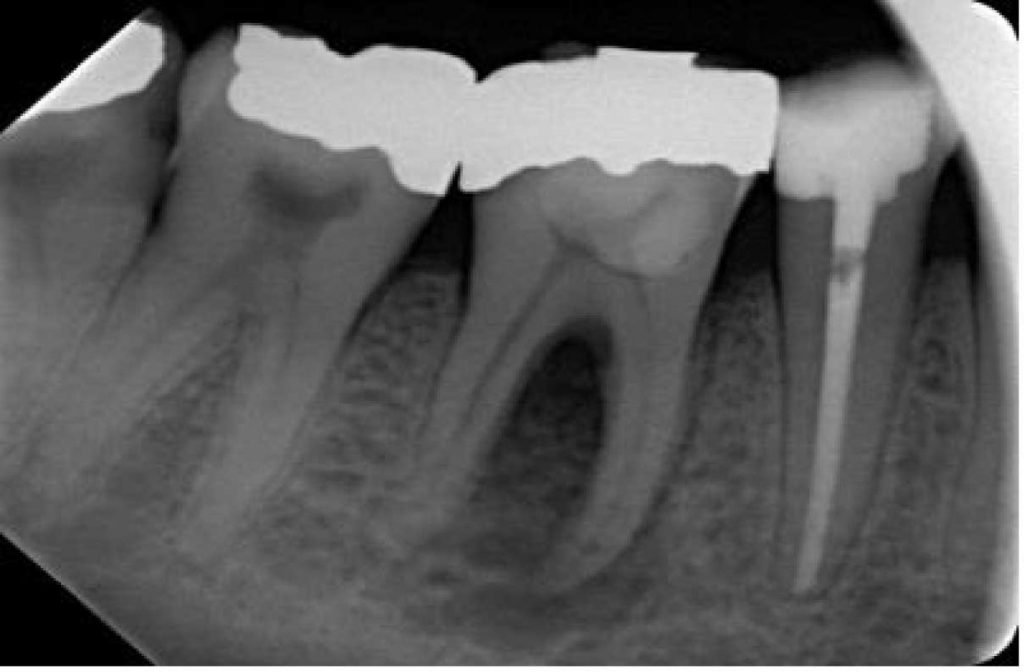

- Przypadek 1. Wsteczna choroba przyzębia – zmiana pierwotnie endodontyczna z szerzeniem się przez więzadło ozębnej.

- Przypadek 2. Jatrogenne uszkodzenie przyzębia – perforacja korzenia.

Streszczenie: Współistnienie chorób przyzębia i schorzeń endodontycznych często stanowi dla lekarza ogromne wyzwanie w aspekcie rozpoznania, leczenia i ustalania rokowania. Postrzeganie procesu chorobowego poprzez relacje przyczynowo-skutkowe między miazgą a otaczającymi tkankami przyzębia, wsparte zastosowaniem racjonalnych klasyfikacji, prowadzi do uzyskania pomyślnych wyników leczenia. W niniejszym doniesieniu przedstawiono kilka metod leczenia pacjentów z różnymi zmianami typu endo-perio. Dodano również pewną modyfikację nowej klasyfikacji zmian endo-perio wg Al-Fouzana. Pierwszy przypadek zaliczono do schorzeń przyzębia o mechanizmie wstecznym (tj. zmian pierwotnie endodontycznych z szerzeniem się przez więzadło ozębnej). W drugim przypadku rozpoznano zmianę jatrogenną w obrębie przyzębia, spowodowaną perforacją korzenia, w trzecim – również zmianę jatrogenną w obrębie przyzębia, spowodowaną urazem zęba w wyniku leczenia ortodontycznego. Pierwsze dwa przypadki leczono metodami niechirurgicznymi, zaś w trzecim przypadku zastosowano zarówno leczenie niechirurgiczne, jak i chirurgiczne. U wszystkich chorych uzyskano całkowite wygojenie zmian tkanek miękkich i twardych. Szczególnie przydatne i prowadzące do skutecznego wyleczenia takich skomplikowanych schorzeń endo-perio okazały się: dokładne poznanie wywiadu [...]